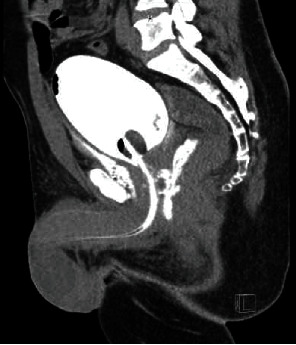

Penetrating posterior urethral trauma from gunshot wounds (GSW) is rare and requires prompt treatment to minimize complications. Data regarding the management of such cases is scarce in the literature and poorly addressed in the guidelines. Different management approaches exist, including urinary diversion with immediate versus delayed urethroplasty/fistula repair. We present our case series to add to our experience to the literature. Three patients aged 18-44 presented with ballistic posterior urethra injuries from GSW. Initial management involved urethral catheter placement, with one patient requiring operative placement of urethral and suprapubic catheters (SPTs). Complications included recurrent membranous stricture, urinary retention, rectourethral fistula, and erectile dysfunction (ED). Posterior urethral injuries from GSW are complex as they can be either isolated or affect adjacent organs. Bladder, ureteral, and urethral injuries must be ruled out. Unlike bladder neck injuries, immediate urethroplasty/fistula repair would be very challenging and not advised for standard prostatic or membranous injuries. Urethral catheter or suprapubic tube is recommended and can result in fistula closure and urethral patency. It is critical to maintain close follow-up with the patient due to the possibility of stricture recurrence. Urethroplasty in a delayed fashion can be very successful.